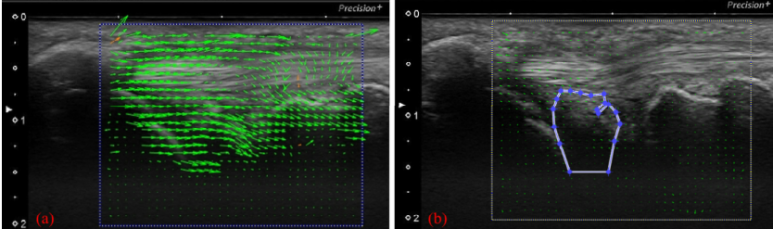

"둘째, 관절이 '과도하게 흔들린다'는 것입니다."

이 연구에서는

'입자 영상 유속계(PIV)'라는

특수 분석 기법으로 관절원판이 움직이는

'속도'를 측정했는데요.

@ https://doi.org/10.3390/s22010345

좌측 건강한 그룹에 비해서

우측 손상된 환자 그룹의 TFC가

더 빠르고 과하게 움직이는 것으로

밝혀졌습니다.

이건 뭘 의미할까요?

삼각섬유연골복합체 TFCC가

손목을 꽉 잡아주는

'안정성'을 잃어버리고,

헐거워진 문고리 마냥 '달그락'거리며

불안정하게 흔들린다는거죠.